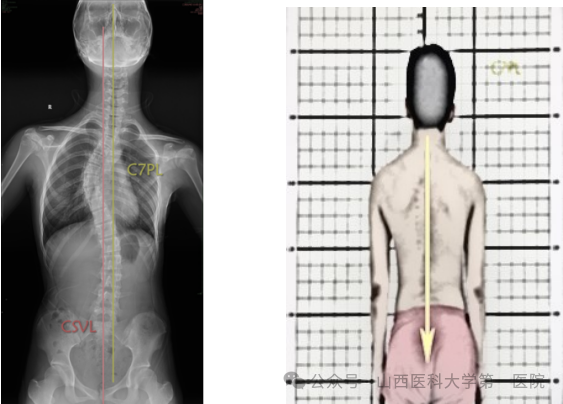

3. 骶骨中心垂直线(CSVL)

从S1上缘中点垂直于地面绘制的垂线,它描绘了脊柱相对于骨盆的冠状位置。

4. C7垂线(C7PL)

C7垂线是C7椎体中心垂直向下的直线,与X线片垂直边缘平行。通过测量C7垂直线与S1(CSVL)中心垂线之间的横向距离,可以确定冠状面的平衡。C7PL-CSVL代表C7PL和CSVL的水平间距。C7PL位于CSVL右侧为正值,左侧为负值,C7PL-CSVL>2cm定义为冠状面失衡。